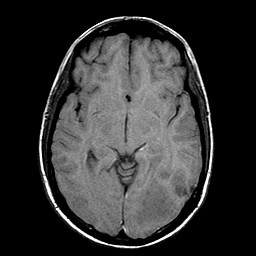

Sarcoma, MR Study #1 mr-t1 -- Slice #10

[Home][Help][Clinical] Slice 10